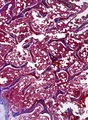

![]() | zawał krwawy płuc | 50%